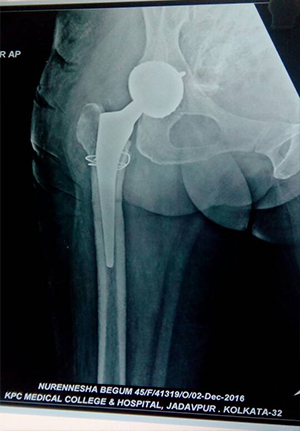

Bipolar hip prosthesis for fracture neck of femure in elder population

Complex primary total hip replacment after failed internal fixation